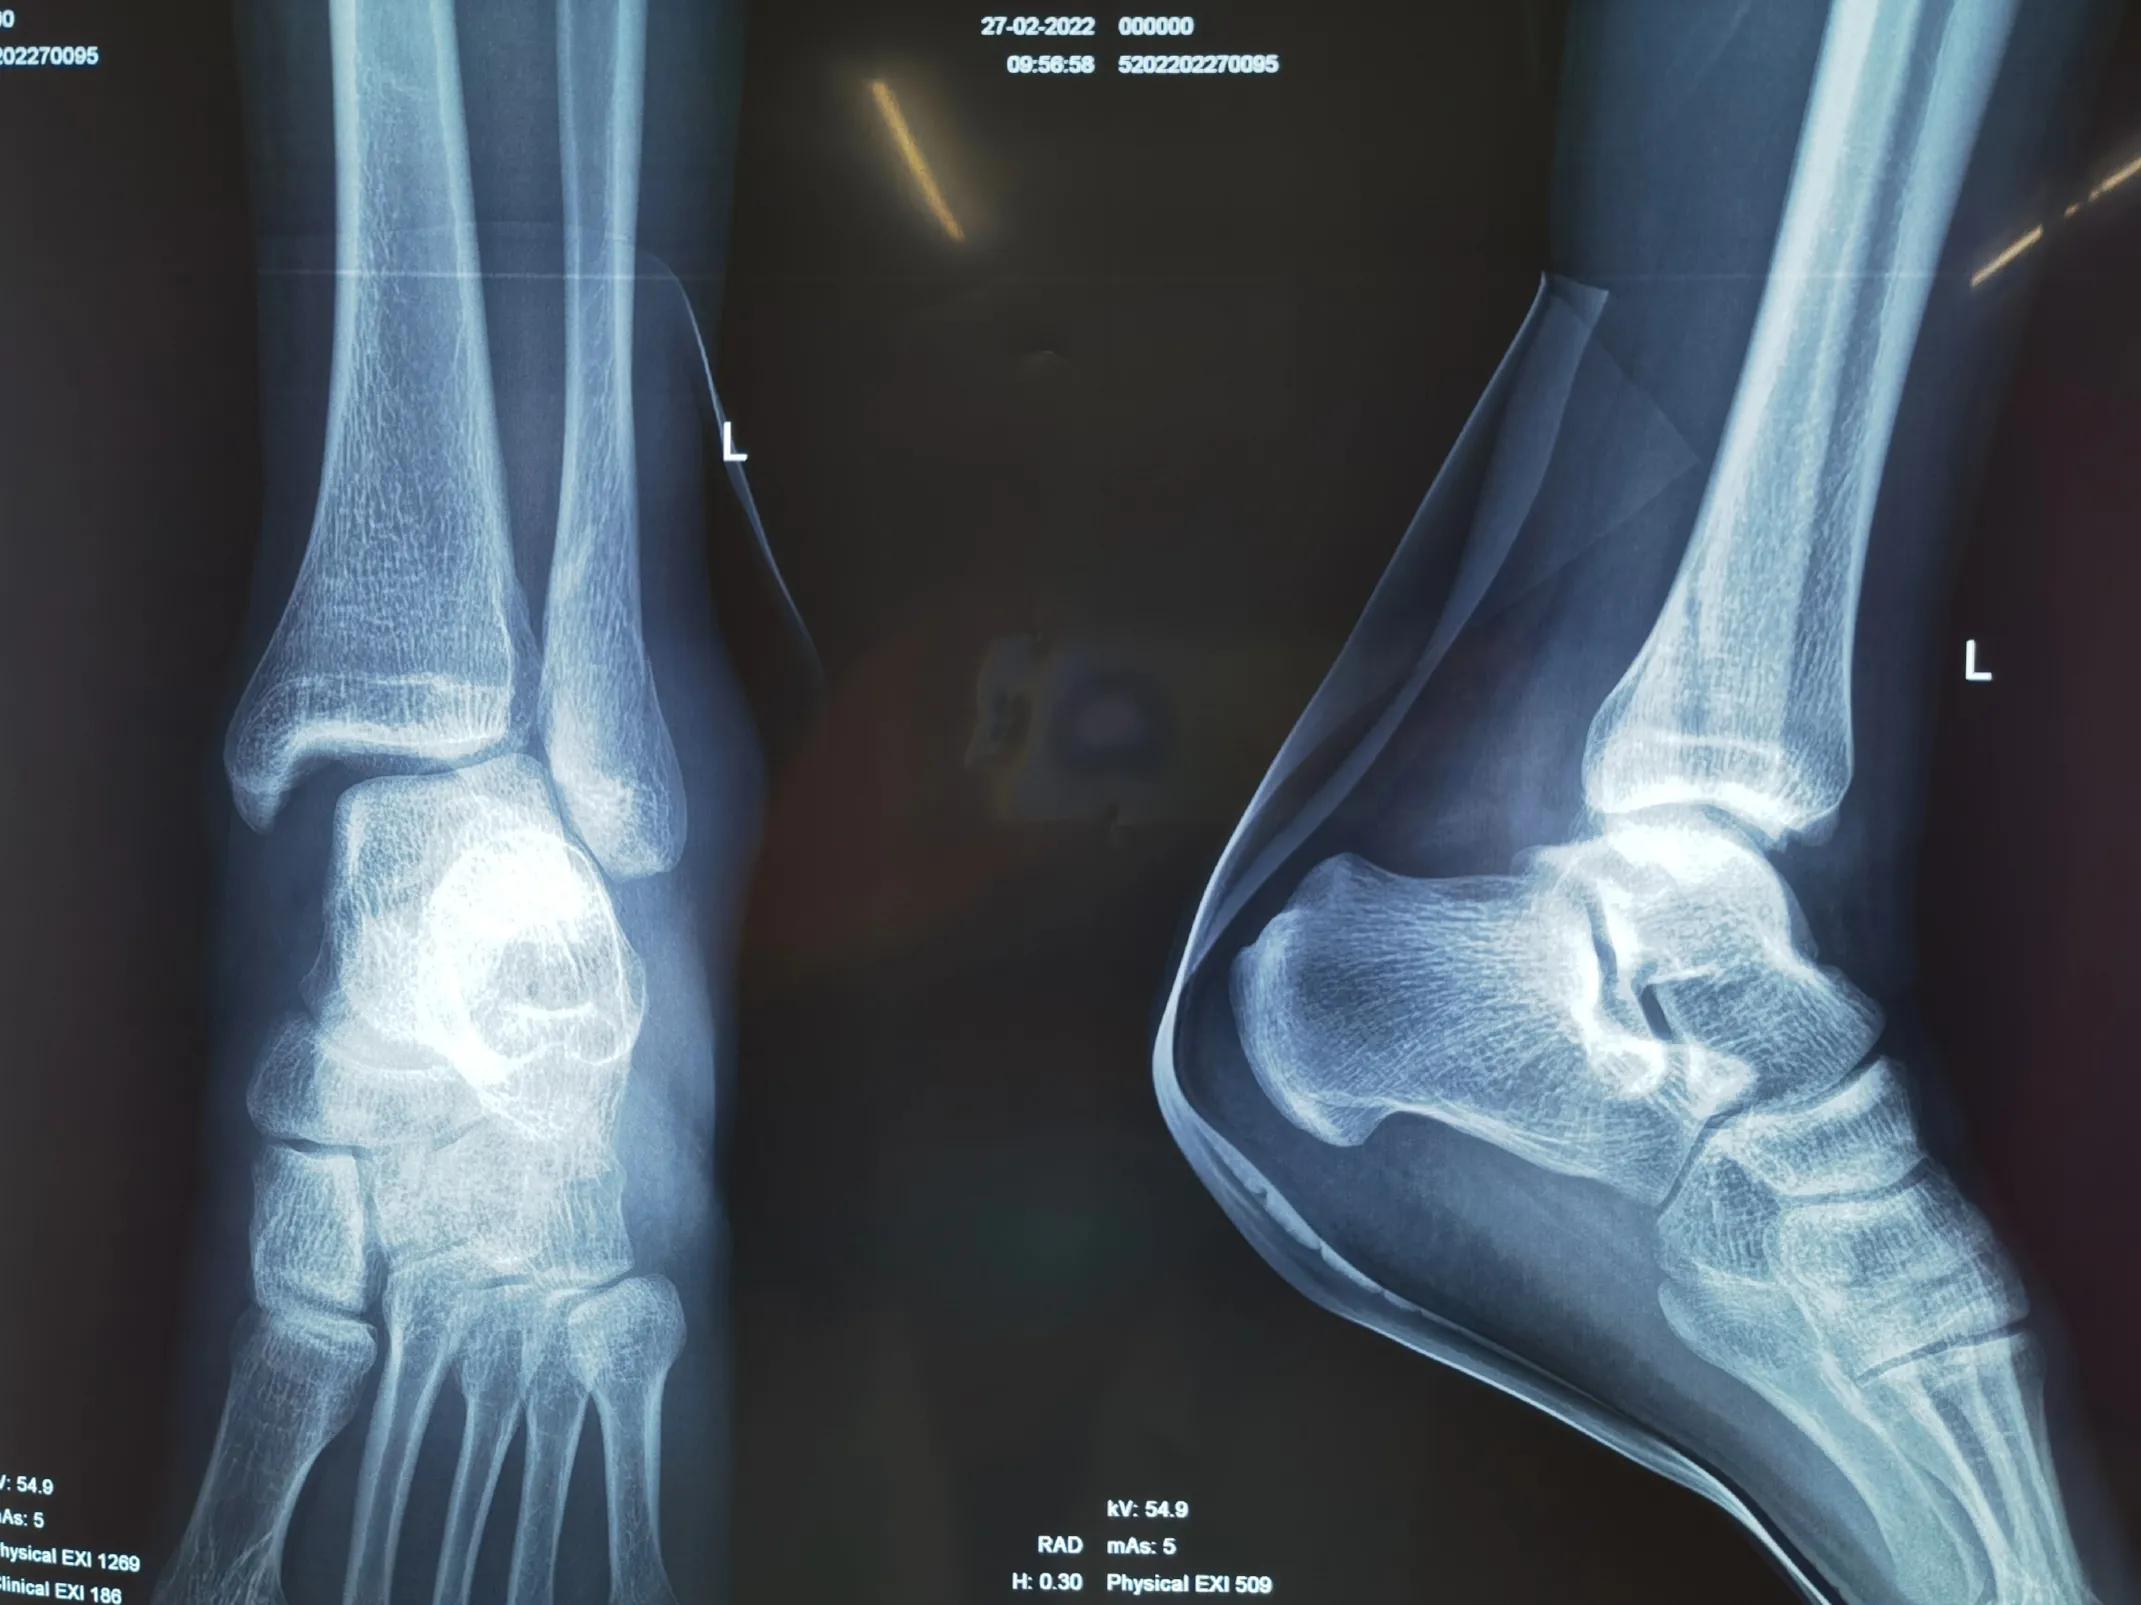

大部分踝关节骨折根据Lauge-Hansen分型可在X光片上判断具体分型及严重程度,判断患者受伤时足的位置和受力方向。临床医师再结合查体可验证患者骨性结构与韧带的损伤的严重程度,预测踝关节稳定性。从而指导临床治疗,决定是否手术及手术方式。

旋后外旋型IV度损伤,三踝骨折伴膝关节半脱位